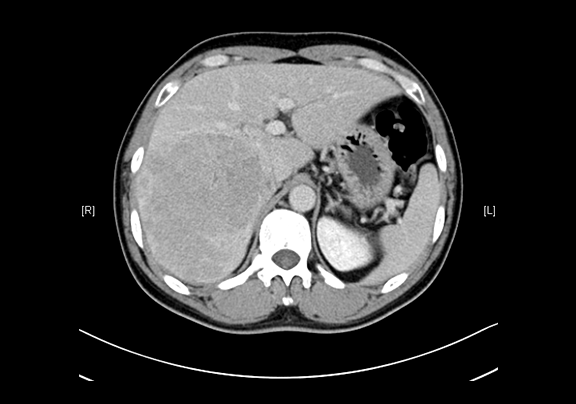

现病史:患者20余天前查体,行腹部超声检查时发现:肝右叶低回声结节,大小约5.8*4.7cm,无腹痛、腹胀,无腰背部放散痛、皮肤巩膜无黄染,无寒战、高热,无咳嗽、咳痰、胸闷、气短,无恶心、呕吐,无腹泻、血便,无尿频、尿急、尿痛、血尿。上腹部动态三维成像(增强)CT检查示,肝右后叶上段占位性病变,肿瘤性病变。

下腹部增强CT示:肝右后叶上段占位性病变,肿瘤性病变,考虑肝癌合并出血可能性大,肝多发小囊肿

术前CT检查:

动脉期

静脉期

平衡期